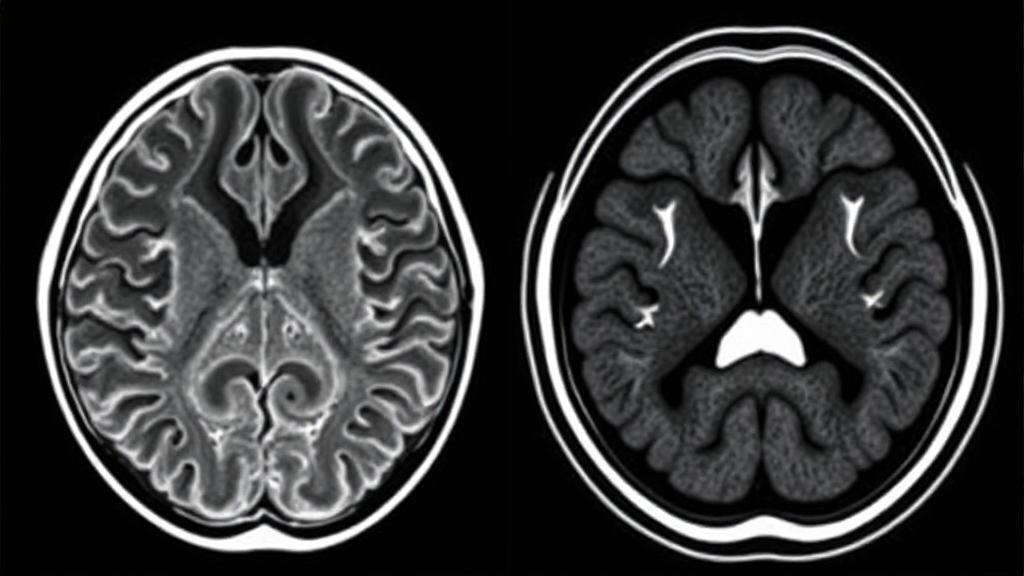

Magnetic Resonance Imaging (MRI) uses strong magnetic fields and radio waves to generate detailed images of organs and tissues. The technology works by manipulating hydrogen atoms in the body's water molecules, producing signals that are converted into high-resolution images.

Computed Tomography (CT) uses X-rays to create detailed cross-sectional images of the body. These "slices" can be viewed individually or stacked together to create three-dimensional representations.

- Superior soft tissue contrast

- Better visualization of white and gray matter

- Excellent for detecting subtle abnormalities

- Multiple imaging sequences available